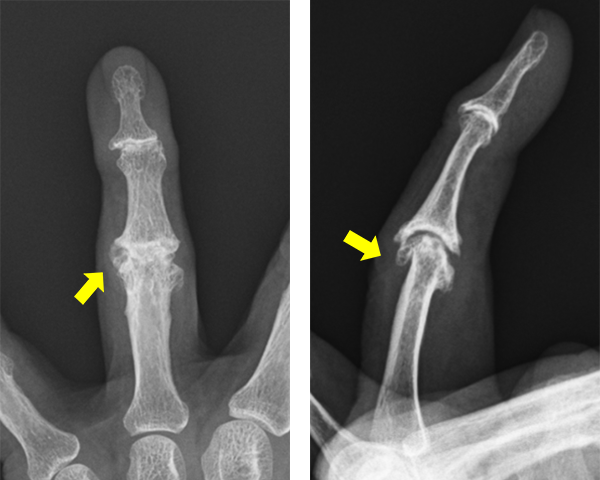

親指のへバーデン結節に合併した粘液嚢腫

へバーデン結節では手指のDIP関節(第1関節)が腫れて痛みを感じるようになります。進行してくるとDIP関節が変形し、変形が強くなると関節の動きが悪くなってきます。

へバーデン結節があるとDIP関節背側(爪の根本あたり)に粘液嚢腫ができることがありますが、これは関節液が皮膚の方に漏れて作られるもので、痛みを伴うことがあります。

また、粘液嚢腫が破れて細菌感染を起こすと強い痛みや発赤、腫脹を伴い、化膿性関節炎や化膿性腱鞘炎などに至ることがあります。